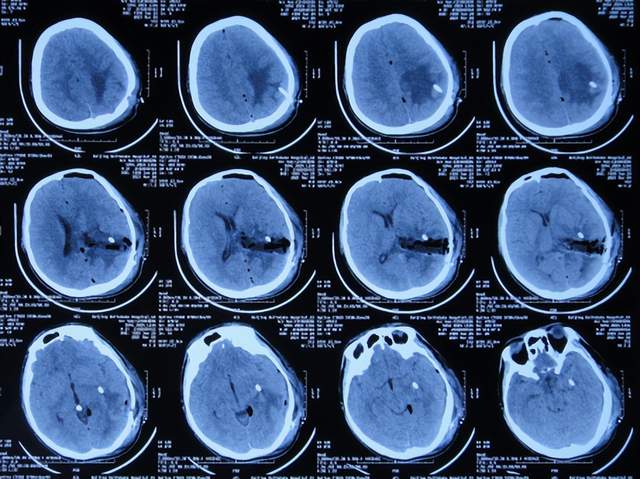

入院后7天即2021年1月20日,进行了颅内占位切除术,留置引流管(图-5)。

图-5:2021年1月20日头颅CT

颅内占位切除术后次日即2021年1月21日,查头颅CT示脑瘤术后改变(图-6)。

图-6:2021年1月21日头颅CT

颅内占位切除术后第2天即2021年1月22日,头痛基本消失,脑瘤病理回报脑膜瘤;查头颅CT示脑室周水肿(图-7)。

图-7:2021年1月22日头颅CT

但术后第4天,出现发热,体温约在38度以上,最高39度,给予对症治疗。

脑膜瘤术后第5天即2021年1月25日,查头颅是示水肿减轻(图-8)。

图-8:2021年1月25日头颅CT

术后第7天即2021年1月27日,拔除脑室外引流管(图-9),改行腰大池引流并给予抗感染治疗。

图-9:2021年1月27日头颅CT

继续抗感染治疗1周的时间,仍精神差,食欲差,间断发热,期间3次查头颅影像(2021年1月29日头颅核磁增强(图-10)、2021年1月31日头颅CT(图-11)、2021年2月3日头颅核磁增强(图-12)均示颞角逐渐有扩张,有感染。

图-10:2021年1月29日头颅核磁增强

图-11:2021年1月31日头颅CT

图-12:2021年2月3日头颅核磁增强